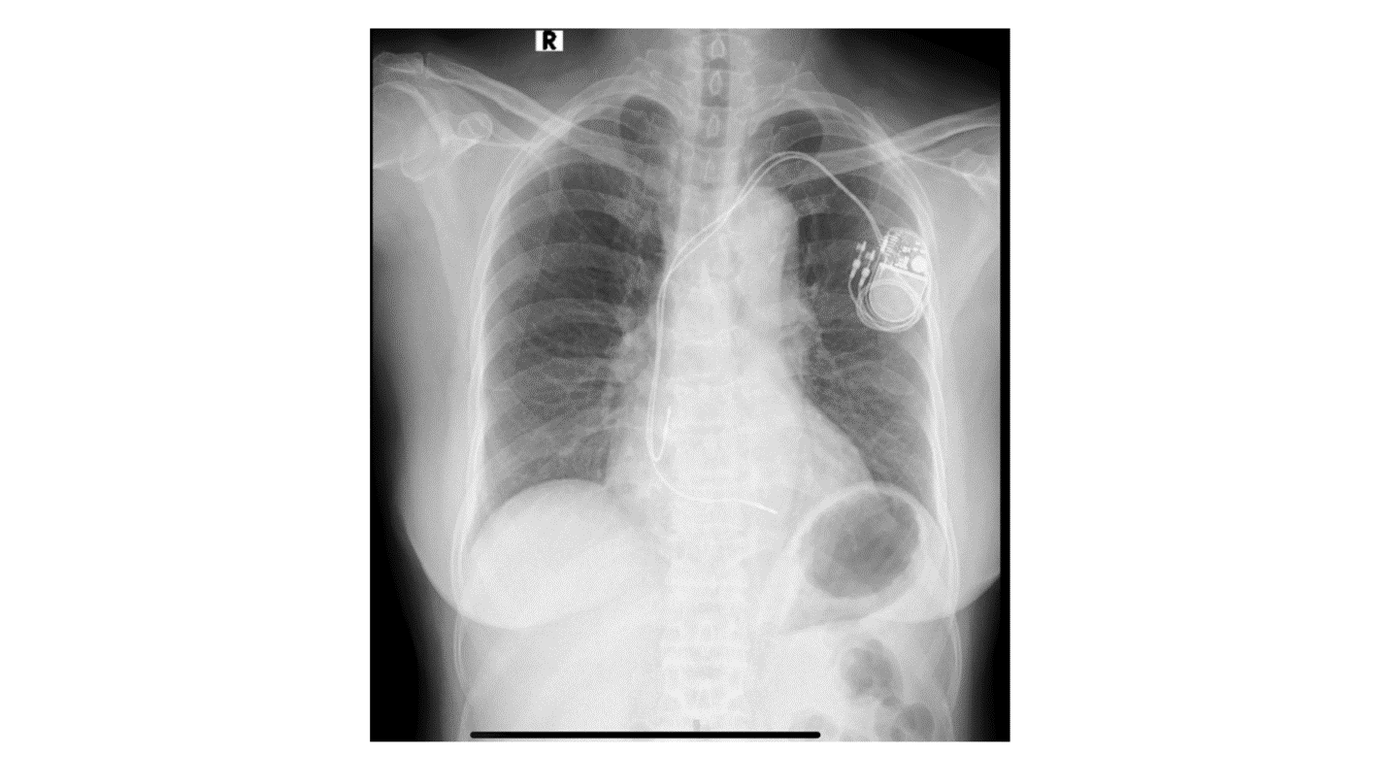

![]() |

| Hình ảnh một ca điều trị rối loạn nhịp tim hiệu quả bằng thiết bị cấy dưới da của bệnh nhân nữ 75 tuổi. Ảnh: Nhật Minh. |